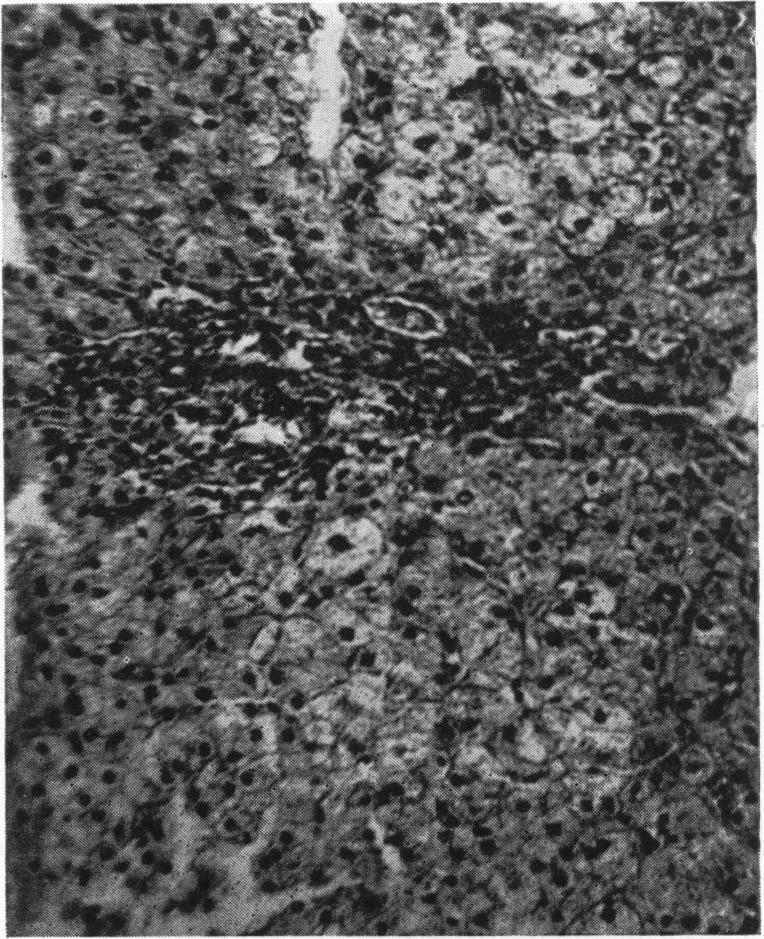

Serum transaminase variations in childhood.

Arch Dis Child. 1958 Oct;33(171):409-12. doi: 10.1136/adc.33.171.409.